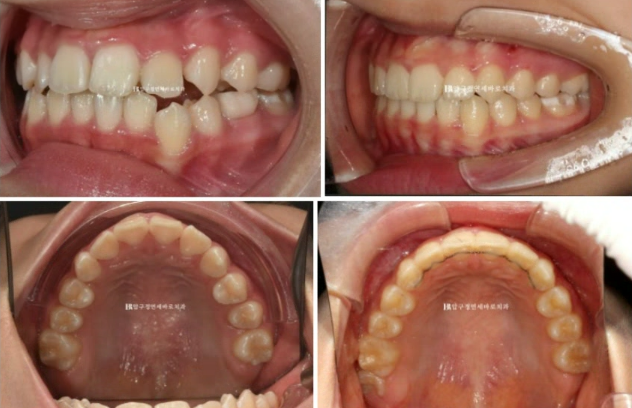

22년 7월 본원에 교정치료를 위해 내원한 만 10세 어린이 입니다.

이미 다른 소아치과에서 교정 중 내원했고 모델활동하는 친구여서 앞니가 가지런해야 했습니다.

일찍이 앞니 4개에 배열용 2D 장치를 부착하고 배열하고 있습니다.

헤드기어라는 상악골 억제 장치도 꼈습니다.

앞니는 가지런해졌지만 비대칭을 고치고 싶어하셨습니다.

엑스레이 분석 상 턱의 비대칭은 아니였고 단지 치아 중심선이 틀어진 것이므로 교정으로 해결이 가능했습니다.

실제로 얼굴 전체로 보면 인중에 비하여 위 앞니 중심선이 한쪽으로 쏠려있었습니다.

아마 본원 오기 전 타 치과에서 헤드기어로 치료했다고 하는데 좌우 힘의 균형이 안 맞으면서 생긴 부작용으로 생각됩니다.

오른쪽 교합은 나쁘지 않습니다.

23.08

왼쪽은 3급 교합관계 때문에 왼쪽 어금니는 잘 안 물리고 이것이 앞니에 영향을 주어 위 앞니 중심이 인중과 얼굴에 비하여 틀어져 있습니다.